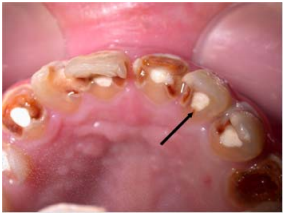

47.與下圖最具相關的診斷為何?

(A)艾迪森氏病(Addison’s disease) (B)白血病(leukemia) (C)貧血(anemia) (D)舔唇皮膚炎(lip licker’s dermatitis)

59 (A)此為磨耗(attrition)症狀 (B)此為酸蝕(erosion)症狀 (C)此為牙釉質發育不全(enamel hypoplasia)症狀 (D)此為猛爆性齲齒(rampant caries)症狀

60.承上題,此症狀最合理之治療計畫為何? (A)將患牙拔除,並戴空間維持器裝置 (B)將患牙做牙周刮除術,並給予暫時充填窩洞 (C)將患牙做治療,並戴不銹鋼牙冠 (D)將患牙做填補,並印模送技工做義齒

74.根據世界衛生組織(WHO)1997年出版的口腔健康調查基本方法(Oral health surveys,basic methods)第四版標準,下圖箭頭所指的牙齒有臨時填充物,其牙齒狀況應記錄為何?

(A)健康(sound) (B)齲蝕(decayed) (C)已填補(filled) (D)外傷(trauma)